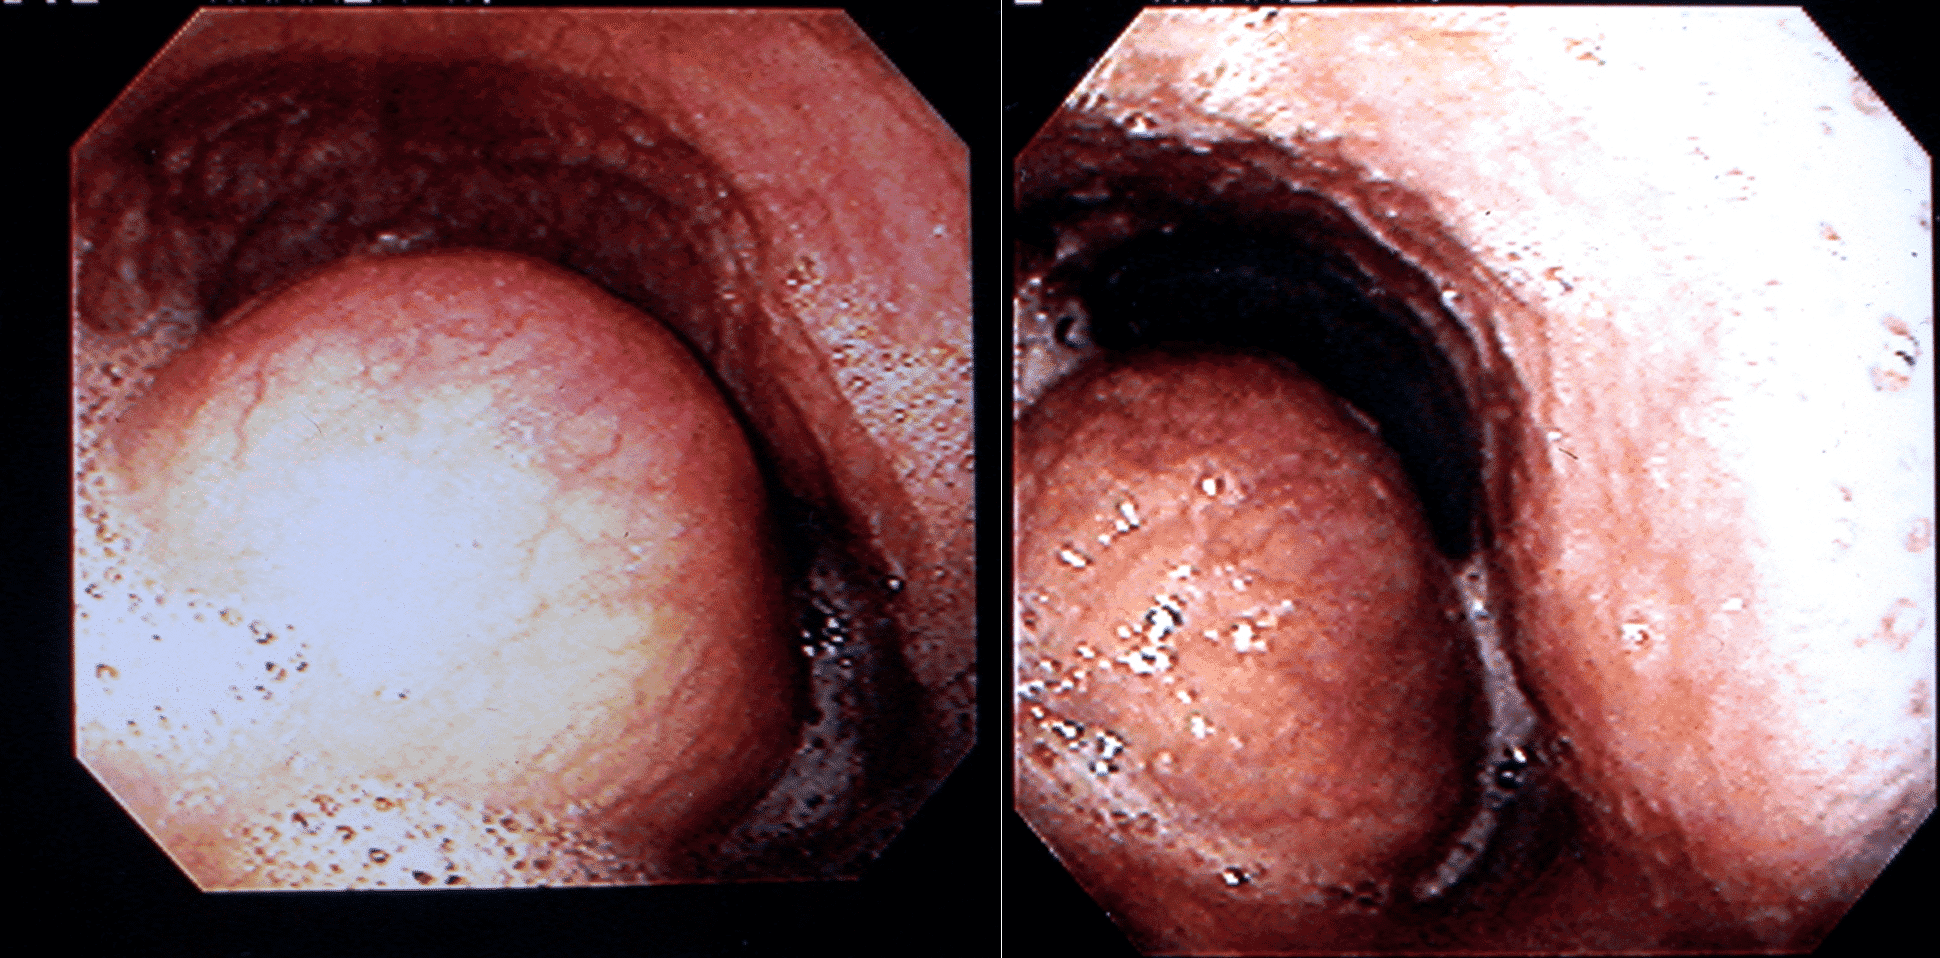

Лейоміоми стравоходу в основному діагностуються, як випадкові знахідки при різних методах візуалізації, під час рутинного скринінгу або обстеження з приводу іншої патології верхніх відділів шлунково-кишкового тракту. Езофагогастродуоденоскопія (ЕГДС) часто виявляє ексцентричне внутрішньопросвітне звуження стравоходу з інтактною слизовою оболонкою над ним (зобр. 1).

Зображення 1. На ЕГДС видно ексцентричне внутрішньопросвітне утворення, що звужує стравохід з інтактною слизовою оболонкою.